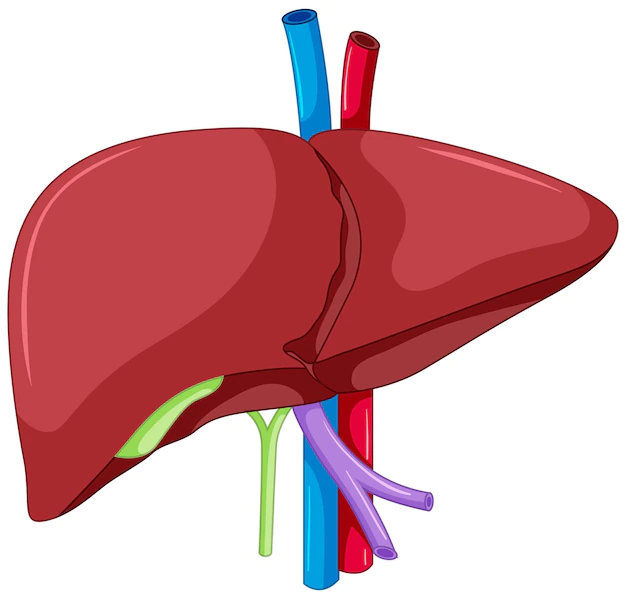

La cara diafragmática se divide en dos superficies, derecha e izquierda, mediante la implantación del ligamento falciforme del hígado. Este ligamento, de naturaleza fibrosa, se origina en la parte anterior del hígado y se proyecta hacia arriba, delineando claramente las porciones diferenciadas de esta cara. Esta división estructural añade una capa de complejidad a la anatomía del hígado y subraya su adaptación precisa a las condiciones circundantes.

La configuración anatómica del hígado revela una adaptación específica en relación con la vena cava inferior y las estructuras adyacentes. En la porción derecha de la vena cava inferior, el hígado se desarrolla hacia atrás y arriba en la fosa laterovertebral. Este desarrollo específico sugiere una expansión estratégica del órgano en esta dirección, aprovechando la morfología de la cavidad abdominal.

A la izquierda de la vena cava inferior, se observa que el surco que alberga esta vena está delimitado en su margen izquierda por el lóbulo caudado del hígado. Esta disposición demarca claramente una separación anatómica entre el lóbulo caudado y el lóbulo izquierdo del hígado, evidenciando una organización precisa de las estructuras hepáticas en esta región.